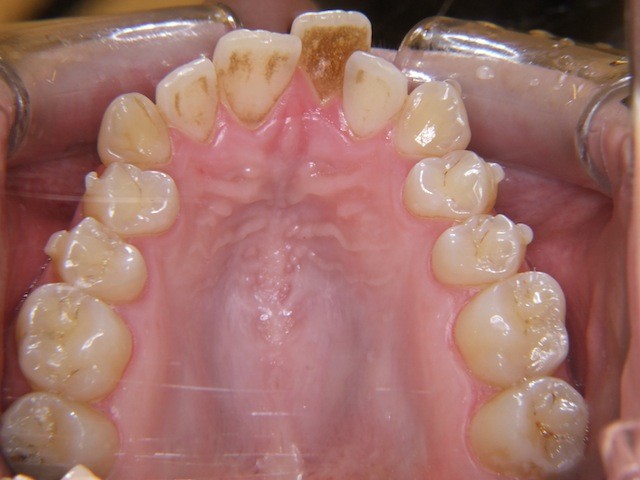

Vorher ----------------------------------- Nachher

Bilderserie Invisalignbehandlung Oberkiefer mit Stabilisierungsdraht am Schluss. Man beachte die Ansammlung von Belägen und Verfärbungen infolge Nischenbildung am Zahn der am meisten im Engstand steht.